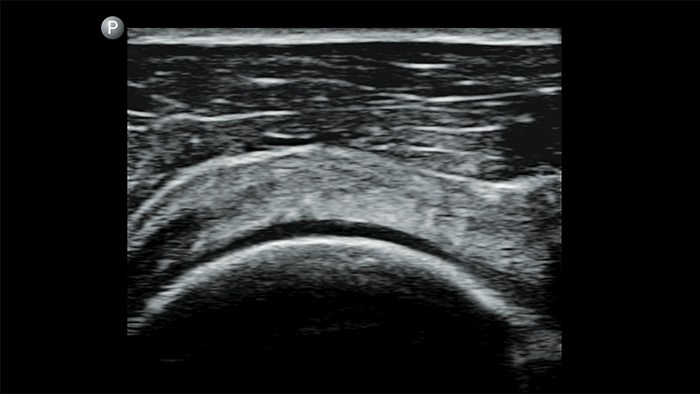

Fallstudie

Integrating Lumify into a resuscitation environment (Integration von Lumify in eine Reanimationsumgebung)